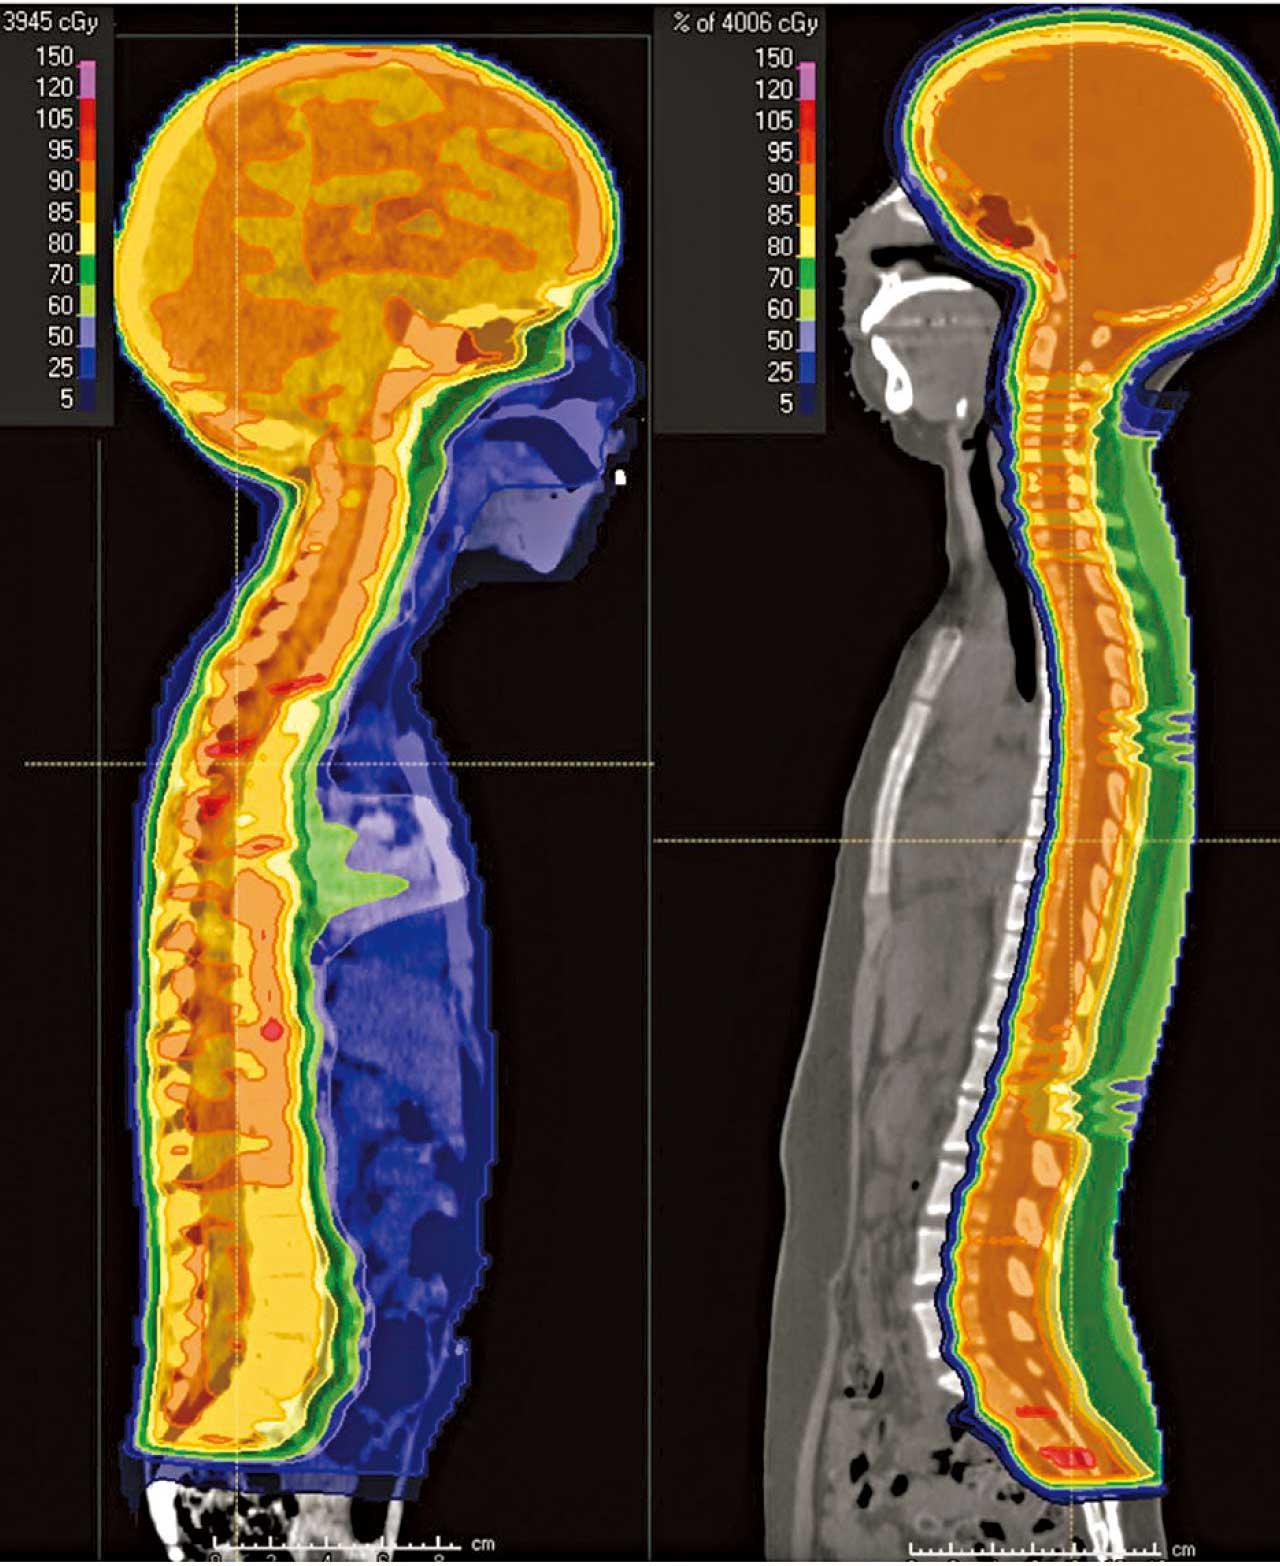

兒童腦瘤個案,質子治療(右)比傳統放射治療(左)可減低面部、頸部、胸腔及盆骨等的輻射承受量。

另一個重點是兒童癌症的應用,研究指癌症兒童5年存活率達85%,但放射治療的副作用會在多年後陸續浮現,逾六成康復者出現慢性健康問題。「以腦癌個案為例,質子治療可集中治療腦部和脊椎,大減其他器官的輻射劑量,減少對兒童成長發育的阻礙,包括認知能力、智商、骨骼發展及內分泌系統等;日後因治療而引發正常組織出現癌症的風險亦較低。」